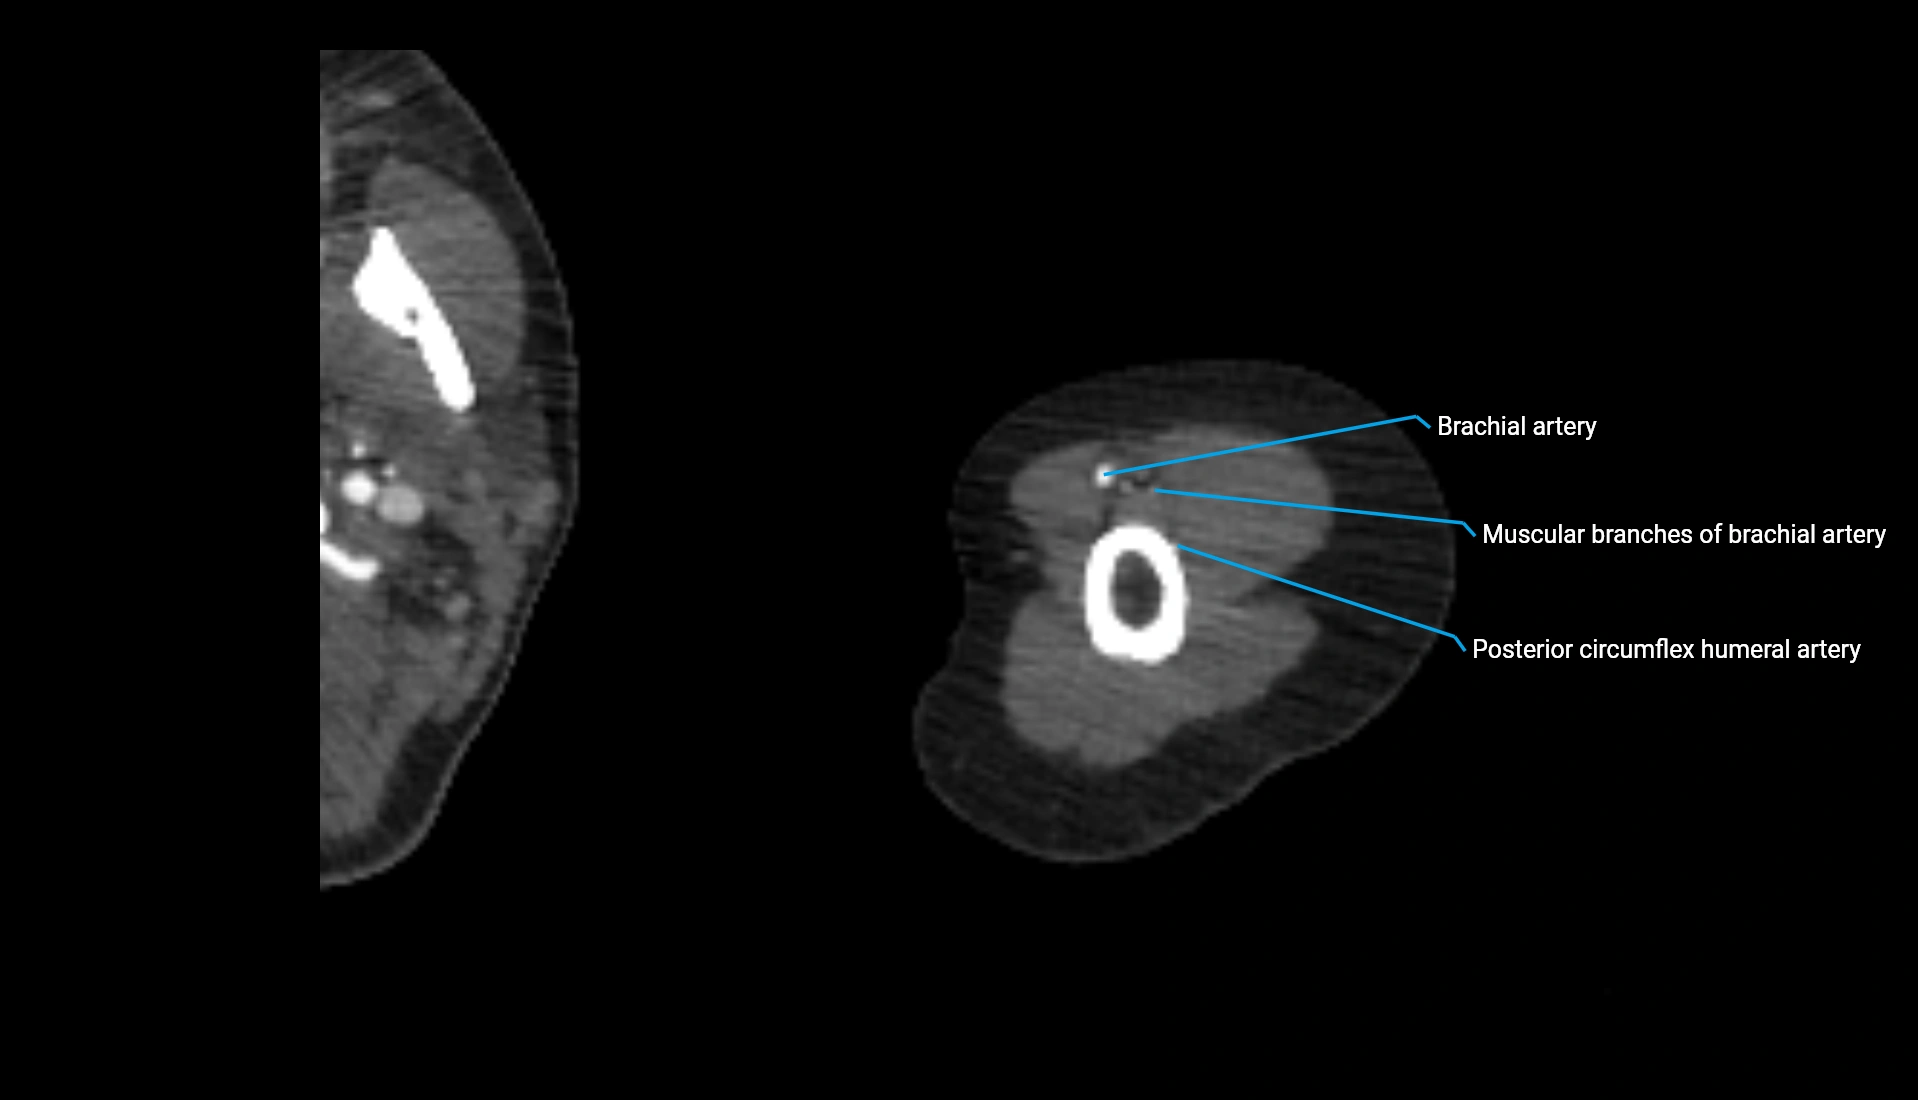

CT Appearance

Non-Contrast CT:

• Cortex: High-density, sharply defined

• Subchondral bone: Dense cancellous matrix

• Articular surface: Smooth concave contour articulating with the capitellum

• Excellent for evaluating bone integrity, alignment, and subtle fractures